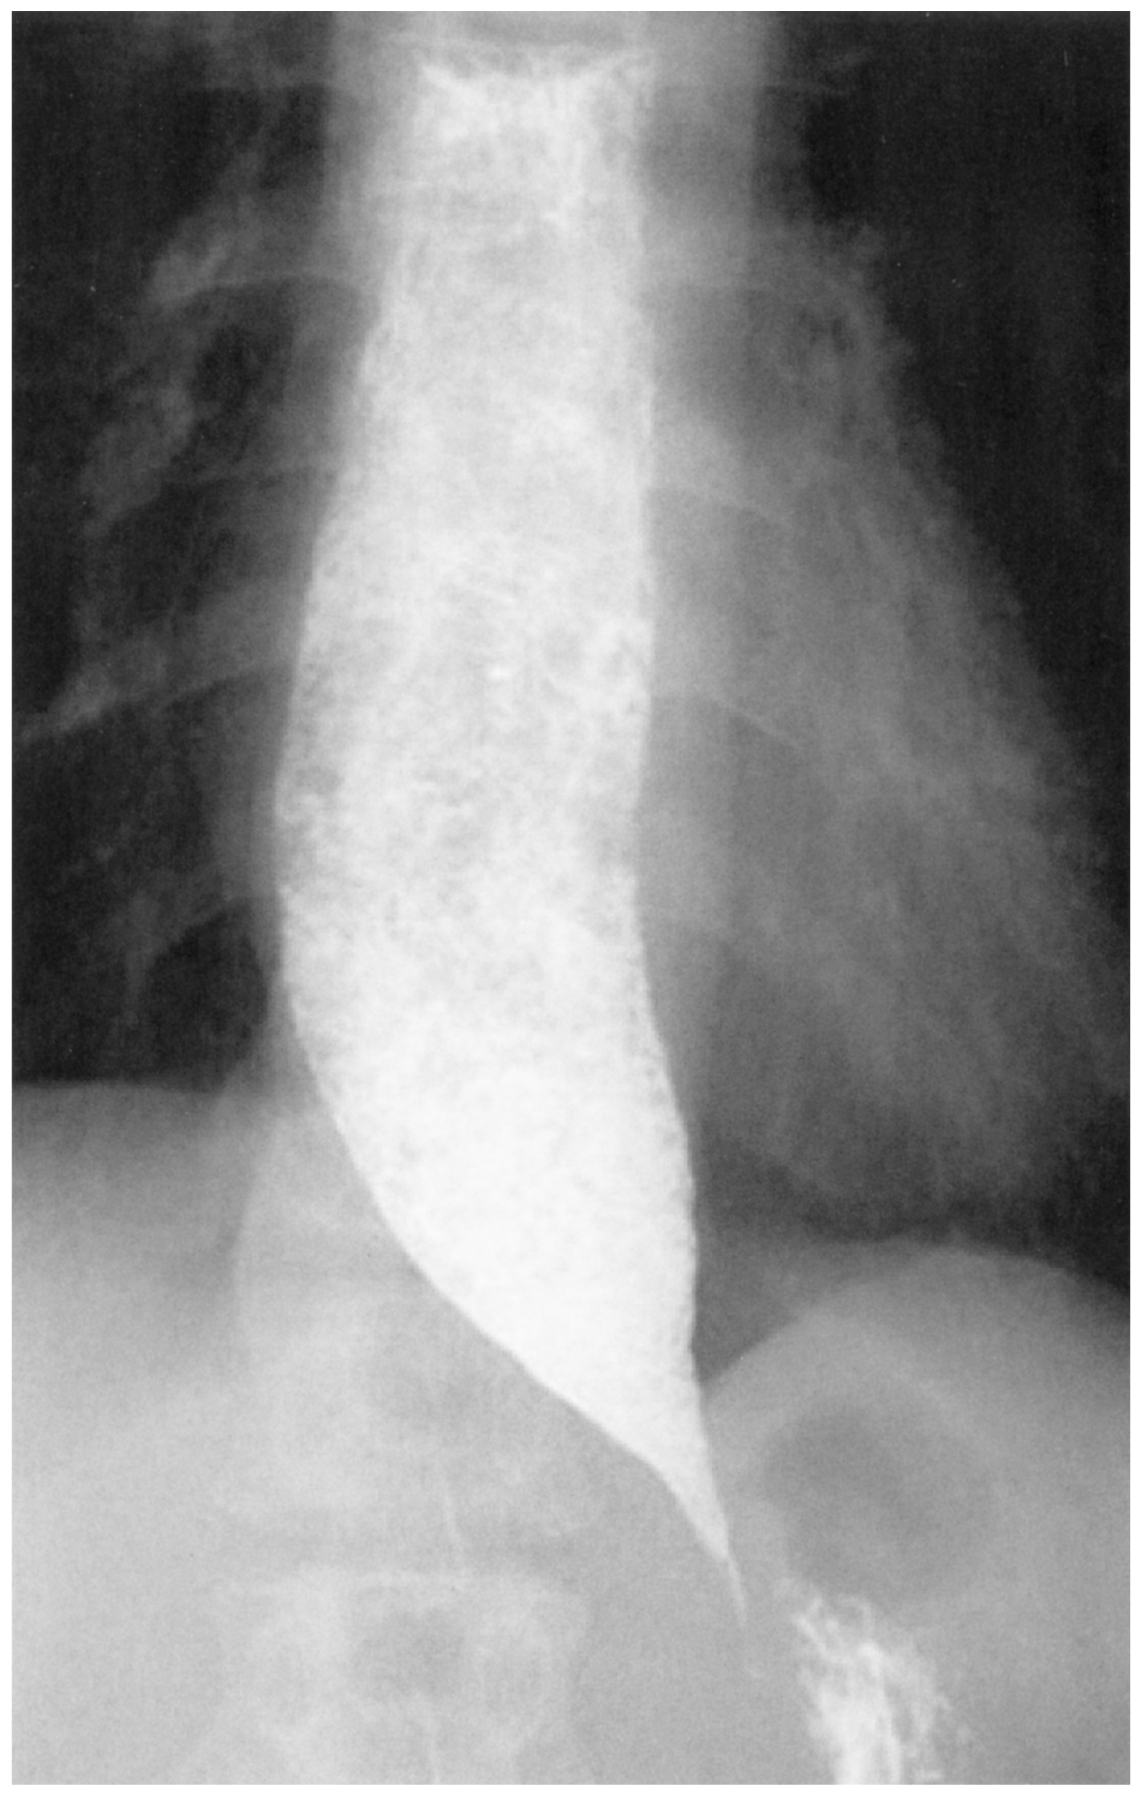

77歳の女性。つかえ感を主訴に来院した。15年前から食物摂取時に胸のつかえ感が時々あった。3か月前から食後に嘔吐を起こすようになり受診した。意識は清明。身長148cm,体重40kg。体温36.7℃。脈拍72/分,整。血圧104/74mmHg。呼吸数14/分。SpO2 98%(room air)。眼瞼結膜は軽度貧血様で,眼球結膜に黄染を認めない。甲状腺は触知しない。頸部リンパ節の腫大を認めない。心音と呼吸音とに異常を認めない。腹部は平坦,軟で,圧痛を認めない。血液所見:赤血球352万,Hb 10.7g/dL,Ht 31%,白血球8,700,血小板20万。血液生化学所見:アルブミン3.3g/dL,総ビリルビン1.2mg/dL,AST 31U/L,ALT 22U/L,LD 231U/L(基準124~222),CK 50U/L(基準41~153),尿素窒素30 mg/dL,クレアチニン1.1mg/dL,Na 136mEq/L,K 5.1mEq/L,Cl 99mEq/L。CRP 0.8 mg/dL。上部消化管造影検査の食道像を下に示す。